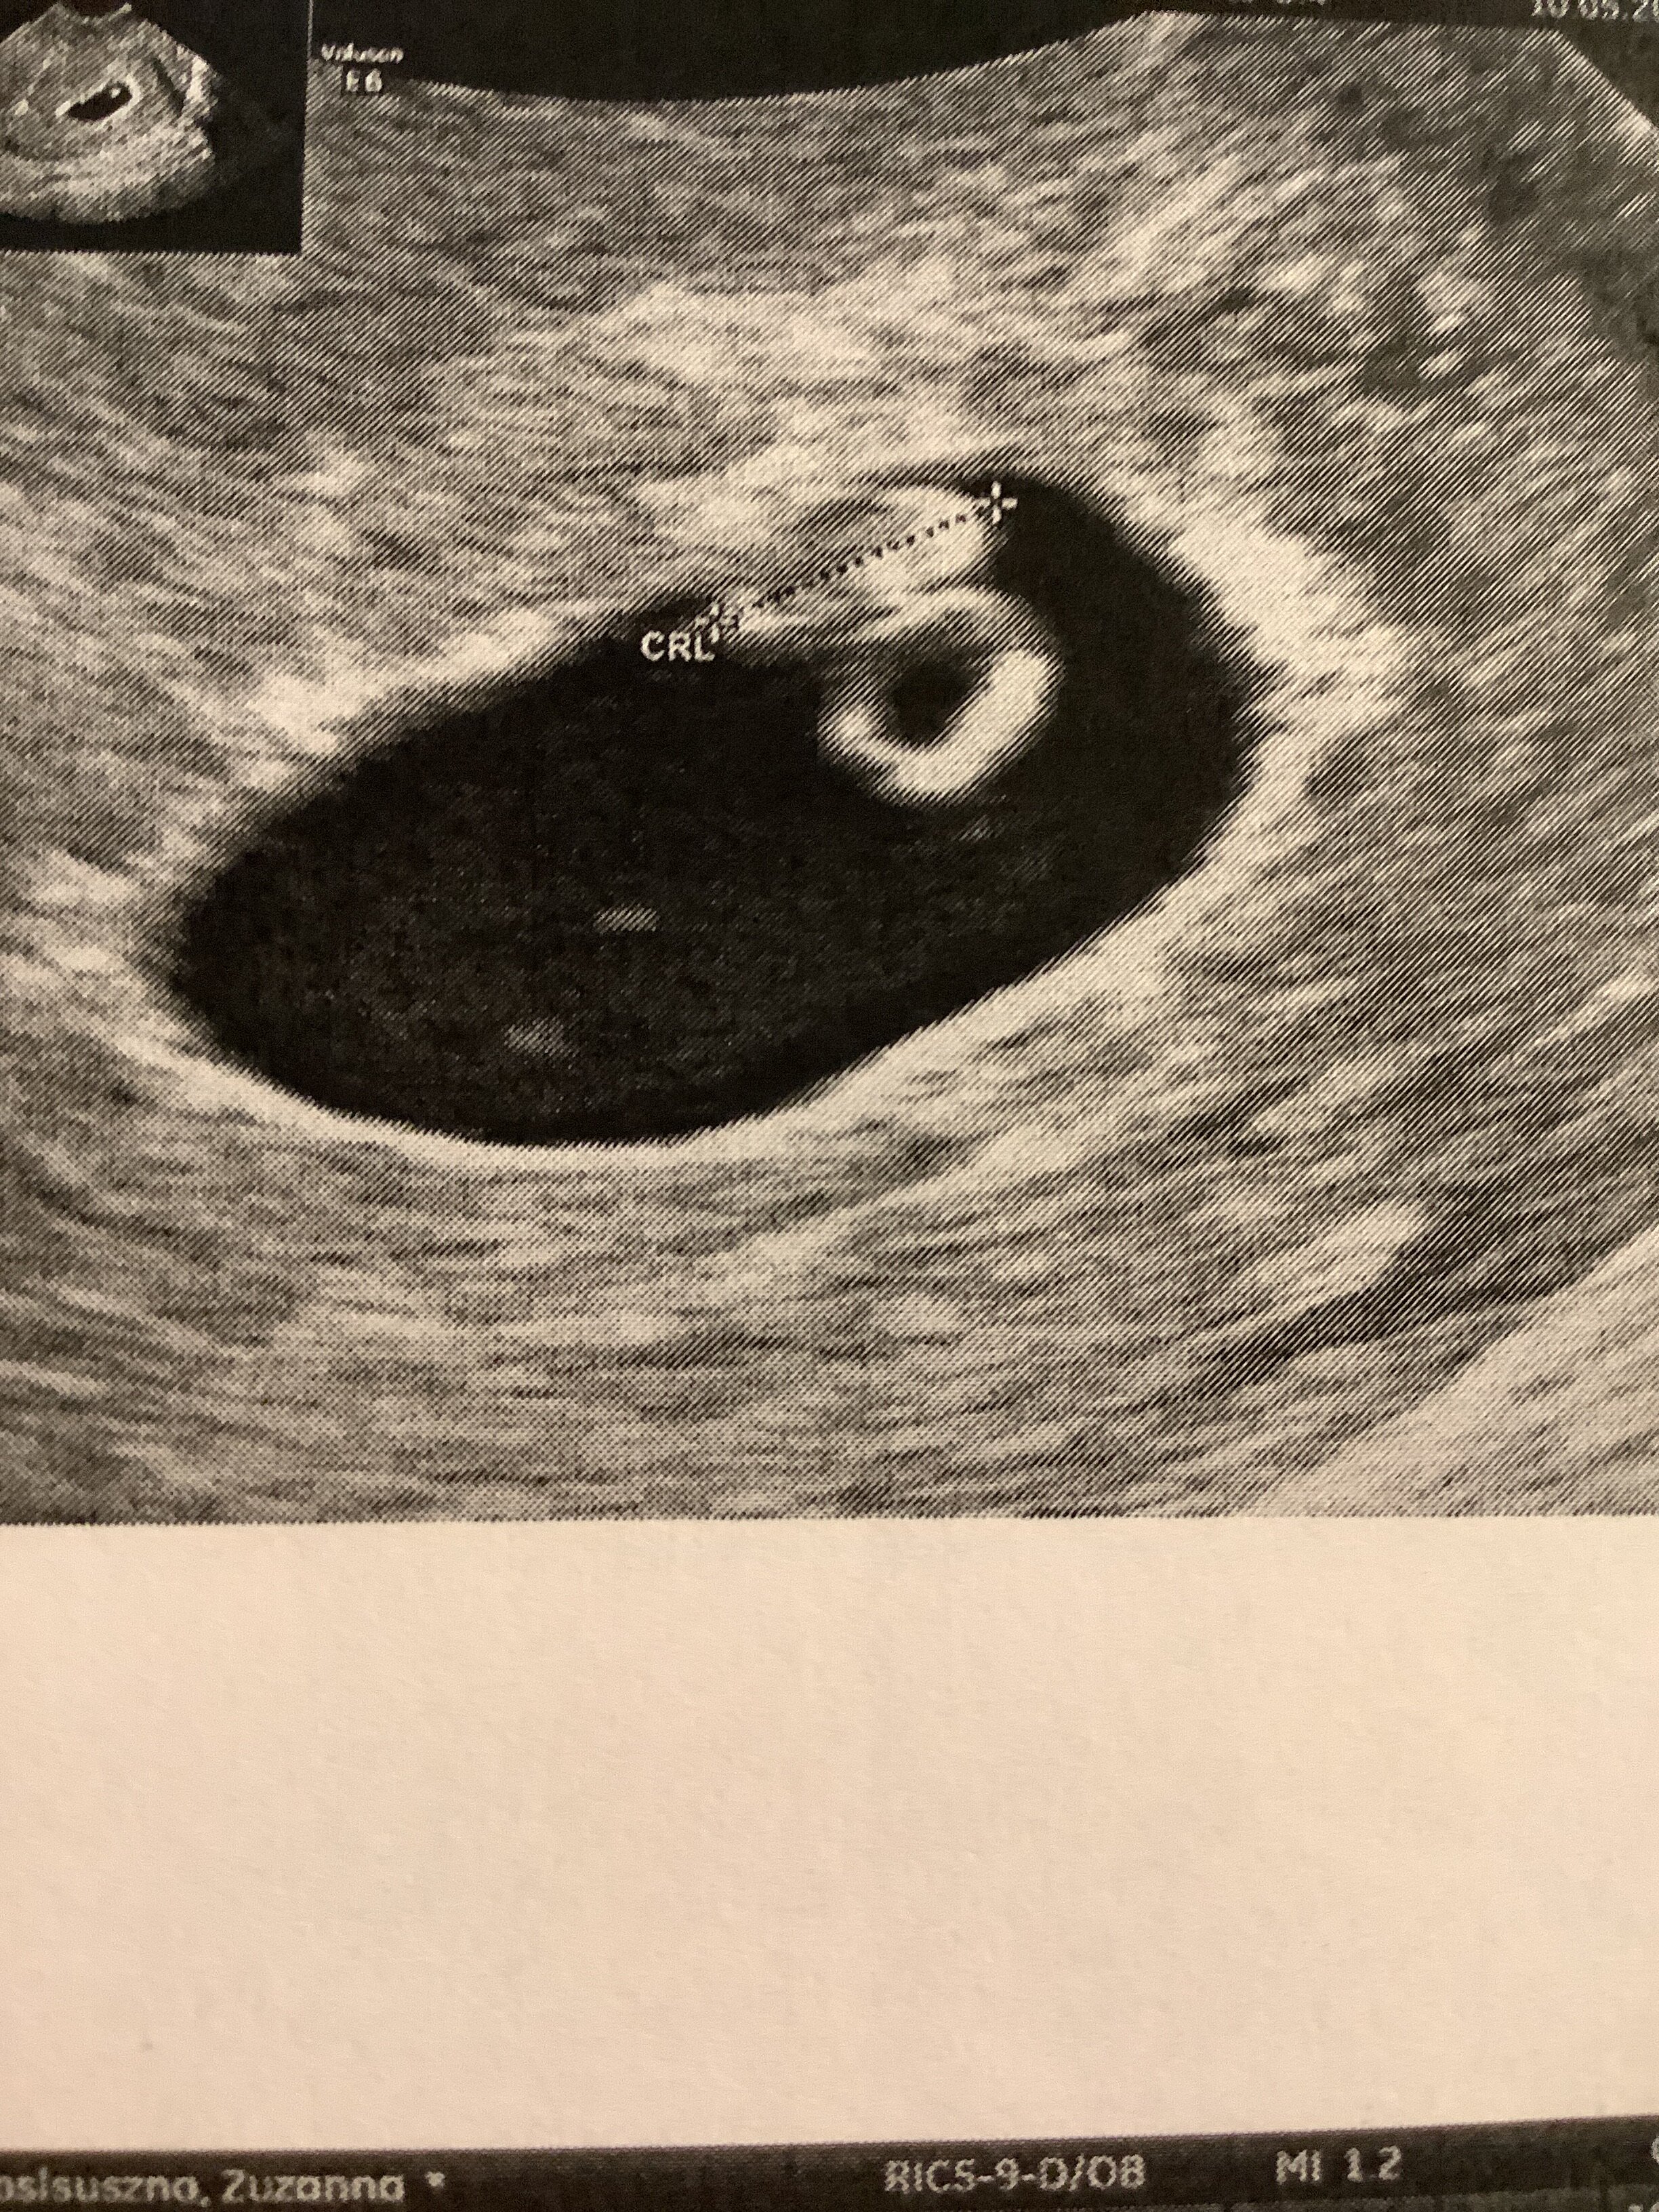

Realnie okazało się, ze to max 11w2d, wiec prenatalne się nie odbyły (płód 40mm, minimum to 45mm), więc pojechałam trochę na darmo, a do tego nie ma wyników mojego NIFTY, które zostało pobrane w 10w, wiec teraz w gruncie rzeczy za wcześnie i czekamy, az wróci pusty wynik